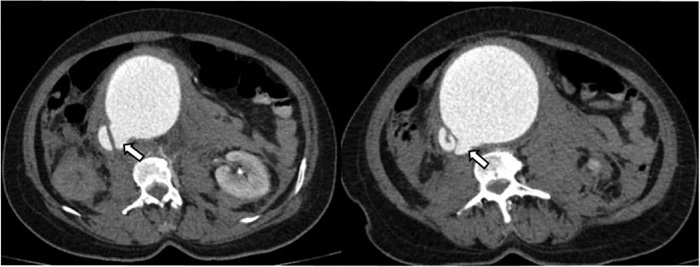

Durante la evaluación de las imágenes, se documentó la presencia de úlceras arterioescleróticas penetrantes, así como la presencia de trombo mural en el recorrido de la aorta abdominal (Figuras 5 y 6).

Opacificación temprana de la VCI en la fase arterial 8.

Pérdida de los planos grasos entre la aorta y la VCI 8.

Aumento del diámetro de la VCI 8.

Visualizar la comunicación anormal entre la aorta y la vena cava 6.